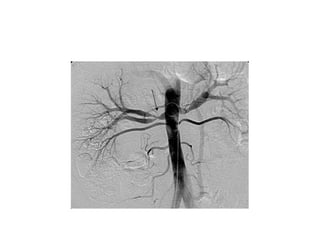

Cathétérisme

• A réserver si besoin de préciser :

– Distribution branches AP

– Anatomie coronaire

• Pressions égalisées à travers CIV

Cathétérisme • Risque dedéclencher des crises hypoxiques • A réserver si besoin de préciser : – Distribution branches AP – Anatomie coronaire • Pressions égalisées à travers CIV